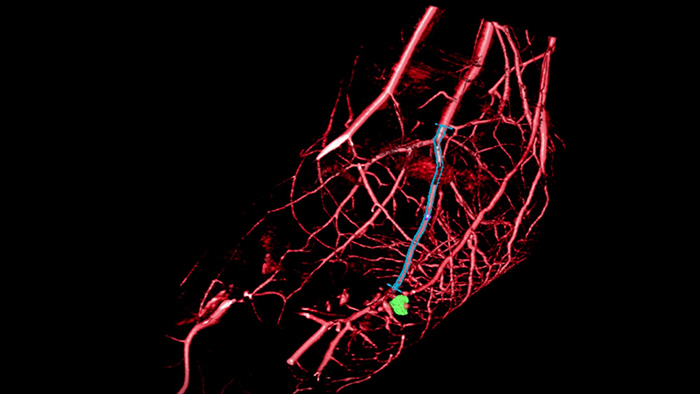

VesselNavigator provides an intuitive and continuous 3D roadmap based on existing CTA and MRA datasets to guide you through vasculature during peripheral procedures.